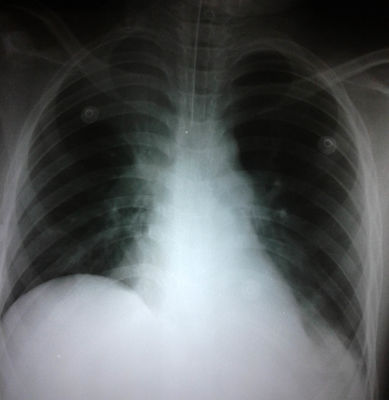

DIA 2 - SALA COMÚN SpO2 = 91-92%, tiraje universal, espiración prolongada, sibilancias en ambos campos pulmonares, subcrépitos en campo pulmonar derecho en vértice. Hemodinámicamente estable. No soplos cardíacos. Se continúa con aerosolterapia, se indica dexmetasona ev, y claritromicina 15 mg/kg/dia cada 12 hs. A las 23 hs del segundo día de internación presenta descompensación aguda, con FC 116 x', FR 32 x', SpO2 89% con máscara con reservorio. Se inicia serie de broncodilatadores durante 1 hora sin respuesta. El médico reviere hipoventilación generalizada, a predominio en campo pulmonar izquierdo, y subcrépitos en vértice de campo pulmonar derecho. Pasa a Unidad de Cuidados Intermedios. Se le realiza goteo de ketamina y sulfato de magnesio. No mejora. Se inicia Bipap geniuno con mala adaptación y respuesta. 23 hs médico de UCI pide cama en UTIP. Placa de torax con atrapamiento apereo y atelectasia del vértice del pulmón derecho. Gases art: 7.37/38.6/62/22/-2.5/92% PCR = 2.7 ¿Qué situación tiene el paciente actualmente?

Answer

• CRIA con alkalosis respiratoria compensada

• CRIA con acidosis respiratoria compensada

• CRIA con acidosis respiratoria descompensada